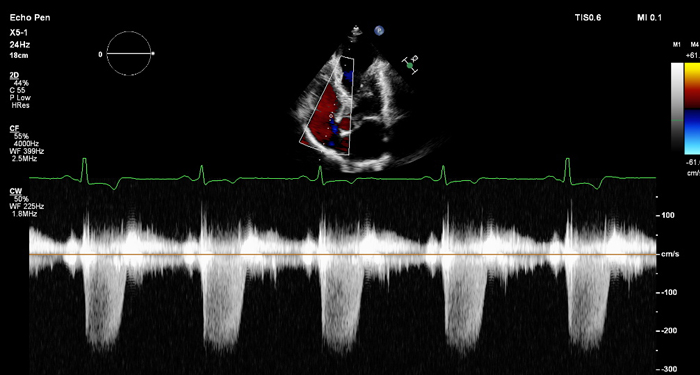

At the touch of a button, the new MaxVue high-definition display brings extraordinary visualisation of anatomy with 1,179,648 additional image pixels compared to a standard 4:3 display format mode. MaxVue enhances ultrasound viewing during interventional procedures and provides 38% more viewing area to optimise the display of dual, side/side, biplane, and scrolling imaging modes.

MaxVue offers a 38% greater viewing area.